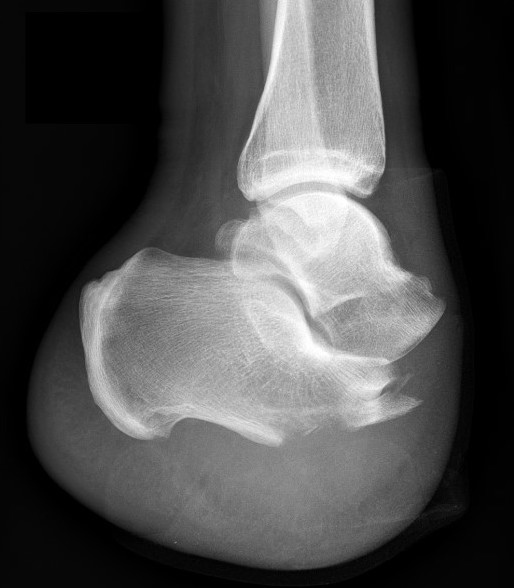

Syme's amputation

Concept

- ankle disarticulation

- remove talus and calcaneum

- remove both malleoli

- preserve heel pad

Technique

- incision from tip of lateral malleolus to medial malleolus across front of ankle

- then continue plantar under sole between same points / MT bases

- need to preserve large post heel pad

- excise talus & calcaneus

- remove malleoli at level of joint & contour

- divide arteries / veins / nerves above levels of flaps

- anchor heel pad to anterior tibia via intra-osseous sutures

Issues

- small surface area / risk of ulcers

- LLD of 4 - 7 cm

- custom AFO